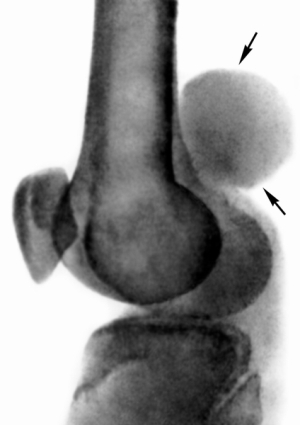

Синовиома коленного сустава начинается с возникновения болей в суставе или в мягких тканях. Если опухоль имеет мягкую консистенцию, то болевой синдром выражен не так сильно. Однако боль нарастает по мере роста новообразования и при разрушении им окружающих тканей и кости. Боль при этом сопровождается некоторым ограничением движения в поражённом суставе.

При пальпации можно чётко прощупать опухолевидные образования, которые могут иметь размер от 2 до 20 см, при этом они могут иметь мягкую или плотную консистенцию. Наиболее частые места их расположения – суставы или мягкие ткани, например, синовиома стопы.

Синовиома левой стопы и подошвы ступни, а также суставов и других мягких тканей, диагностируется при помощи самых разных методов, например, это может быть рентгенография, компьютерная томография, ангиография, радиоизотопное исследование, биопсия с последующим цитологическим и гистологическим исследованием.

Первоначальное исследование – а это рентген и КТ, а также радиоизотопное сканирование, позволяет определить опухоль, её местоположение и размеры. Ангиография помогает определить в образовании наличие разросшихся сосудов.